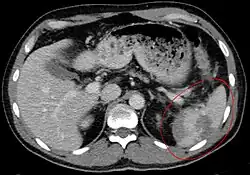

Rupture traumatique de la rate

Un scanner de l'abdomen peut donner un aperçu plus complet des blessures spléniques et autres, pouvant montrer une fracture, des lacérations ou un hématome sous-capsulaire. La gravité des lésions peut être ainsi classée[9] ce qui permet une optimisation de la prise en charge et une diminution sensible de la nécessité d'une prise en charge chirurgicale[10].